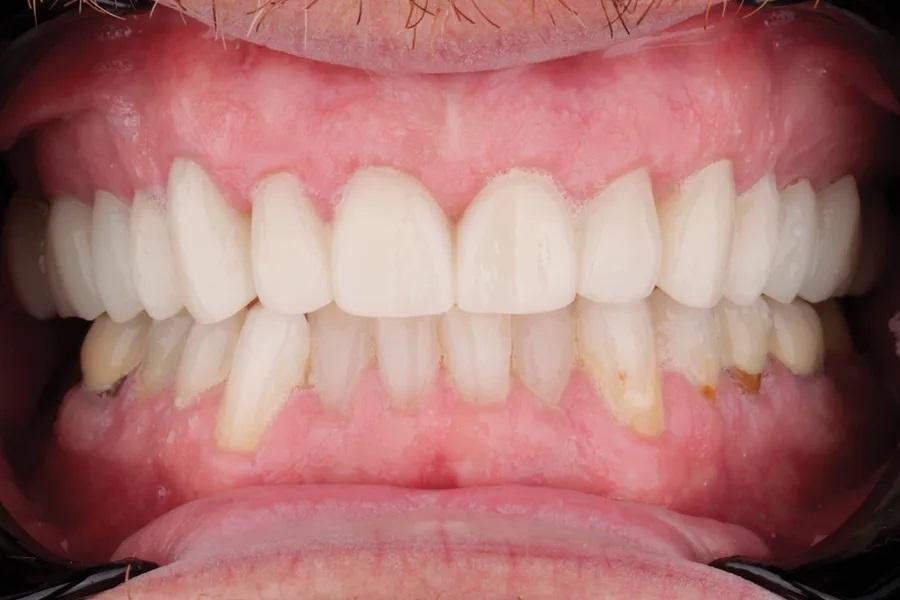

Мужчина, 45 лет. Основная жалоба — неловкость при улыбке из-за коротких, деформированных и измененных в цвете зубов. Обследование выявило гингивит с соответствующей потерей прикрепления, множественные кариозные поражения, износ зубов и реставраций (Фото 1 – Фото 3). Зафиксирован ограниченный паттерн жевания (ОПЖ), что определило умеренный функциональный риск и необходимость учета окклюзии в плане лечения.

Фото 2. Улыбка крупным планом до лечения.

Фото 3. Вид с ретракторами до лечения. Износ, истончение эмали, окрашивание зубов.